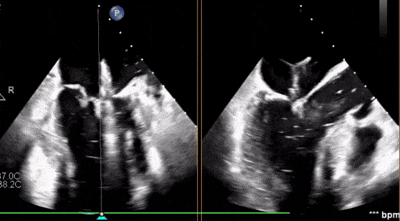

術(shù)后超聲

反流變?yōu)檩p度,反流等級(jí)從4+降為1+;

術(shù)后平均跨瓣壓差1mmHg;

夾子夾合量:前葉15mm,后葉10mm;

剩余瓣環(huán)面積:術(shù)后有效瓣環(huán)面積3.7cm²;

二尖瓣3區(qū)可見(jiàn)夾子強(qiáng)回聲,位置固定。

術(shù)前術(shù)后對(duì)比

術(shù)后